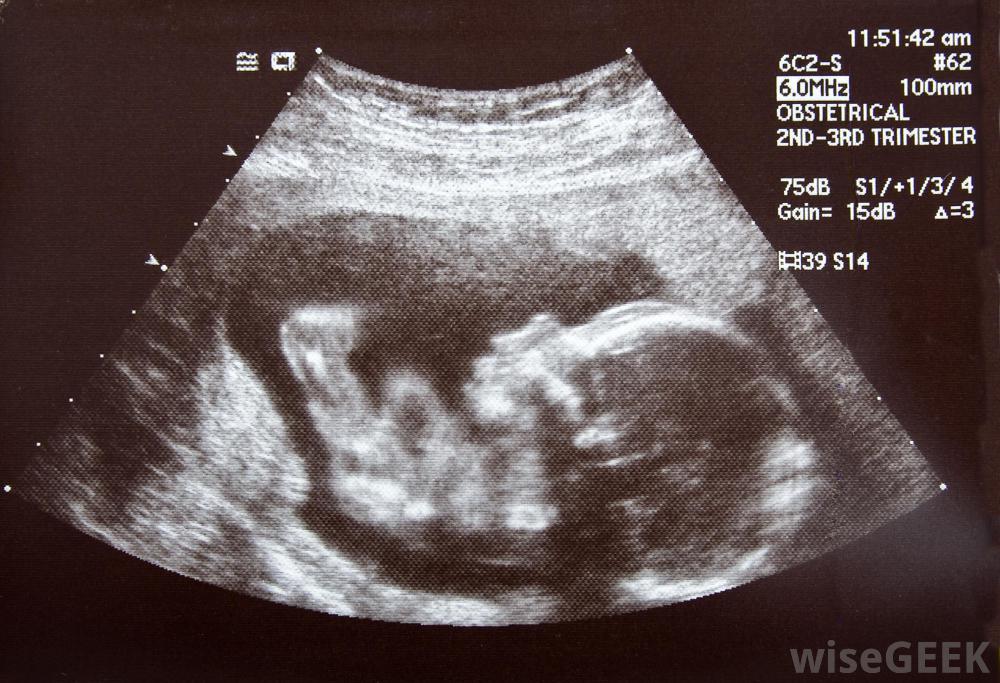

什么是胎兒缺氧(Fetal Hypoxia)?

胎兒缺氧本身并不是一種疾病,它是發生在子宮內的一系列病理過程,使胎兒在一段時間內嚴重缺氧,造成損傷和損傷。器官活動和代謝過程紊亂,可能發生先天性異常中樞神經系統,包括大腦和呼吸障礙是常見的,會導致缺氧缺血性腦病、腦癱、多動癥、癲癇等多種神經和神經精神疾病。在許多情況下,死亡率很高,雖然孩子可以存活下來,但突然產子的風險很大死亡綜合征(SIDS)高發,胎兒缺氧可增加某些嬰兒猝死綜合征的風險在許多情況下,胎兒缺氧缺氧的確切時間和原因尚未被發現。其結果是父母和醫生認為胎兒缺氧是導致缺氧的原因。例如,在缺氧缺血性腦病中,輕微的情況可能表現為肌肉張力差、短暫進食,哭鬧和睡眠異常,神經系統疾病在出生后三到四天后才變得接近正常。中度疾病會導致嬰兒昏睡,在出生后24小時內幾乎沒有深部肌腱反射、睡眠呼吸暫停和癲癇發作。嚴重的這種細胞神經疾病典型的昏迷或昏迷,對身體刺激無反應,呼吸不規則,視力異常,癲癇發作,無吸吮能力嚴重形式的風險包括心跳不規則、血壓變異和心血管衰竭。在許多胎兒缺氧的情況下,死亡率很高胎兒宮內或胎兒缺氧,以及由此導致的圍產期腦損傷,導致了巨大的時間和金錢成本,包括為幸存者提供持續的終身治療,據世界衛生組織(WHO)估計,全球每年有400萬至900萬新生兒死亡,約120萬人死亡,嚴重殘疾的幸存者人數大致相同輕度至重度缺氧缺血性腦病患者,終身治療可使存活率達到60%。胎兒缺氧的初步治療嬰兒是指將出生的嬰兒立即浸入低溫療法中以增加存活的機會。影像學研究通常顯示嚴重的腦損傷和一些出血。電解質通常嚴重偏低,需要立即灌注鈉、鉀,以及氯化物以及嚴重減少尿量的治療方法嬰兒通常需要復蘇和穩定,小心的液體管理,支持性通氣治療,以及癲癇發作的抗驚厥藥物。低血糖和高血糖是一個風險,通常會立即開始適當的治療,以獲得良好的營養長期缺氧的胎兒可能會受到損傷或損傷。出生后20到30歲內缺乏自主呼吸出生后神經系統的異常發現通常持續到出生后的7分鐘以上,預后是,如果嬰兒存活下來,其生命將受到嚴重的限制。輕度至重度缺氧缺血性腦病的存活率為60%,需要終身治療和監測。癲癇發作的出現表明預后不良,胎兒缺氧有時與加法缺乏癥(ADD)或影響兒童的神經系統疾病有關出生前20至30分鐘內缺乏自發呼吸幾乎總是死亡的征兆分娩或分娩期間發生的胎兒缺氧可能會給嬰兒帶來終身并發癥。胎兒缺氧可能發生在健康、順利的懷孕之后。